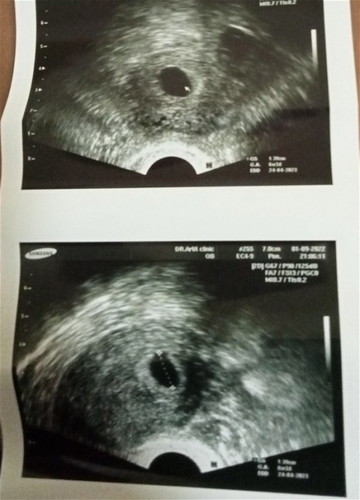

6w3dตรวจหน้าท้องไม่เจอพอซาวด์ช่องคลอดเจอเเต่ถุงเเม่คนไหนเคยเป็นเเบบนี้บ้างค่ะเครียดมากๆค่ะกังวนมากๆ

เราซาวด์ตอน 6 สัปดาห์ 1 วัน พบแต่ถุงตั้งครรภ์ค่ะตอนแรกแอบกังวล วันนี้ไปซาวด์ใหม่ 8 สัปดาห์ 1 วัน เจอตัวน้องและการเต้นของหัวใจแล้วค่ะ☺️☺️ แม่ใจเย็นๆนะคะอายุครรภ์น่าจะยังน้อยอยู่น้องเลยตัวเล็กอาจทำไห้มองไม่เห็นค่ะ☺️☺️

เป็นค่ะ 5 วีค ซาวหน้าท้องไม่เจอ แต่ซาวช่องคลอดเจอ เห็นถุงและท้องในมดลูกค่ะ พอ 7 วีค ซาวหน้าท้องเจอตัวน้อง+ฟังเสียงหัวใจค่ะ แม่อย่าเครียดนะคะ น้องยังเล็กการซาวยังไม่แน่ชัด รอสัก 7 วีคก่อนนะคะ อย่าคิดมากนะคะ

เคยเป็นค่ะ เหมือนกันเลย 6w2d เจอแต่ถุงตั้งครรภ์ ตอนนั้นมีเลือดออกด้วย ตอนนี้น้อง 1ขวบ1เดือนแข็งแรงดีค่ะ ซาวน์หน้าท้องเจอน้องตอน 8w